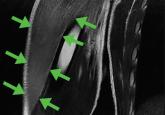

Swelling of both arms and chest after push-ups